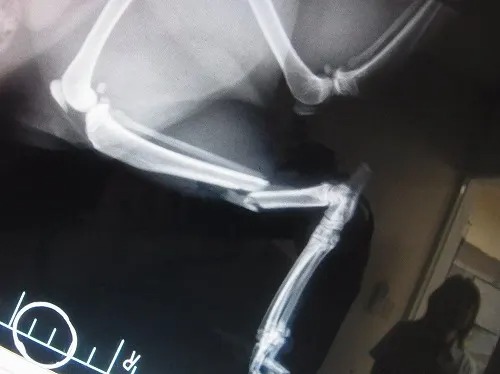

レントゲン写真を撮させてもらいました

バックり折れてます

手術は外からピンを5本打って固定するというやり方です